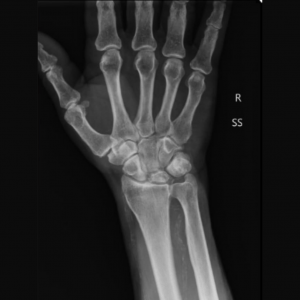

Большинство пациентов жалуются на боль запястье, усиливающуюся при нагрузке. При осмотре определяется болезненность в проекции полулунной кости. Первые шаги для диагностики болезни Кинбека — это сбор анамнеза, осмотр и рентгенограммы. Иногда требуются дополнительные исследования, наиболее информативным из которых является магнитно-резонансная томография. Именно МРТ позволяет выявить нарушение кровоснабжения полулунной кости, когда еще нет изменений на рентгенограммах. Также могут применяться компьютерная томография или остеосцинтиграфия.

В дальнейшем рентгенологически определяются, деформация полулунной кости, сплющивание вдоль продольной оси и укорочение в поперечнике. Контуры кости становятся неровными; в центре определяются участки просветления, которые соответствуют зонам рассасывания кости. Не часто, но отмечаются сужение суставной щели, как проявление деформирующего остеоартроза. Также могут определяться рентгенологические признаки ложного сустава полулунной кости, патологические переломы, полулунная кость может стать фрагментированной, т.е. распасться на части.

Рентгенограмма при болезни Кинбека.

МРТ и КТ являются наиболее чувствительными при диагностике болезни Кинбека; простая рентгенография показывают отклонения позже, как правило, при начале склеротических изменений полулунной кости, сменяющихся кистозными изменениями, фрагментацией и коллапсом.